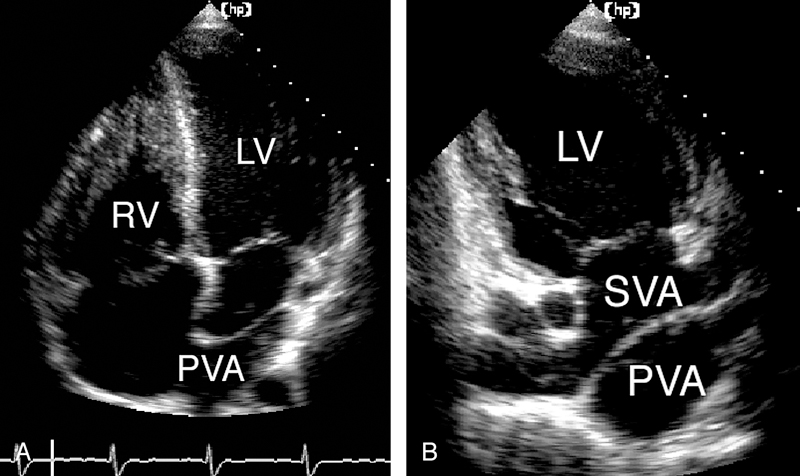

فحوصات تشخيصية لبعض امراض القلب والشرايين التاجية